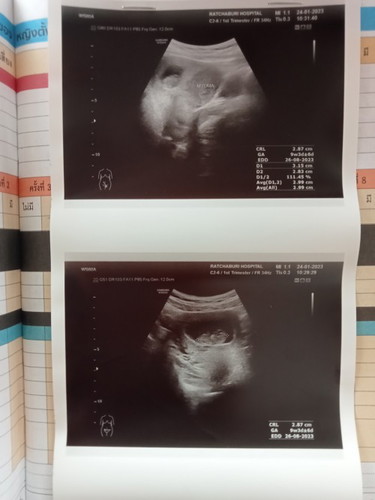

วันนี้ไปหาหมออัลตราซาวด์ตามปกติ แต่ปรากฏว่าเจอเนื้องอกในมดลูก3ซม. แต่คุณหมอไม่ได้แจ้งรายละเอียดอะไรไว้ แค่บอกว่าเป็นเนื้องอก แบบนี้เราสามารถตั้งครรภ์ได้ตามปกติมั้ยค่ะ เสี่ยงอะไรกับแม่หรือน้องมั้ยค่ะ